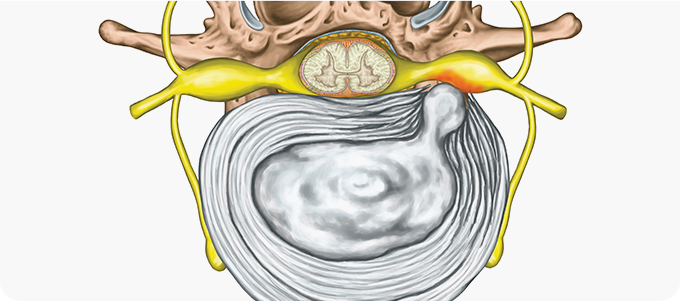

척추관 협착증

신경다발이 통과하는 척추관이

좁아져 신경을 누르는 질환

태어날 때부터 척추관이 좁은 선천적 협착증도 있지만,

나이가 들면서 척추관이 좁아지는 후천적 협착증이

대부분

입니다.

일종의 노화현상으로 척추관 뒤쪽의 인대와 관절이

점차 비대해지고 불필요한 가시 뼈들이 자라 나와

척추관을 누르면서 통증이 생깁니다.

허리 디스크와 척추관 협착증

허리 디스크와 척추관 협착증은 완전히 다른 병이지만 허리보다 다리가 저리다는 증상 때문에 오인하기 쉽고, 두 병이 한꺼번에 나타나는 경우가 많습니다.

허리 디스크는 지속적으로 다리가 아픈 경우가 많지만, 척추관 협착증은 걸을 때만 다리가 아프다는 차이가 있습니다.

허리디스크

허리디스크 관련 이미지

• 허리를 앞으로 굽힐 때 통증이 심해진다.

• 누우면 통증이 감소하고 움지이면 아프다.

• 허리에서 다리까지 당기고 아프다.

• 누워서 다리를 들어 올리는 동작을 할 수 없다.

척추관 협착증 관련 이미지

• 허리를 앞으로 굽힐 때는 별다른 통증이 없지만 뒤로 젖히면 통증이 심해진다.

• 누워 있다가 일어나기는 힘들지만 일단 움직이면 허리가 조금씩 부드러워 진다.

• 오래 걸으면 다리가 저려 잠시 주저 앉았다 걸으면 편하다.

• 누워서 다리를 들어 올리는 동작에 무리가 없다.